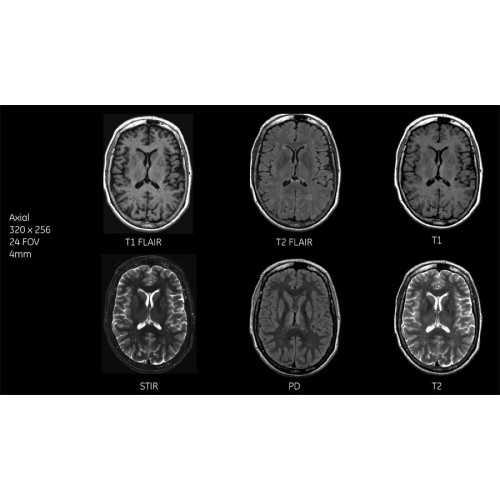

Благодаря революционному программному пакету Silent Suite уровень шума снижается до 77 дБ, что всего на 3 дБ выше уровня окружающей среды. Программный пакет Silent Suite теперь включает полный пакет приложений для исследования ЦНС (T1, T2 FLAIR, DWI10, МРА). Кроме того, мы расширили возможности визуализации Silent за пределы ЦНС для исследований скелетно-мышечной системы и позвоночника. Silent Suite – платформа, содержащая в себе все импульсные последовательности для бесшумного сканирования.

Система SIGNA Pioneer воплощает поразительные достижения в области визуализации. Передовая технология Total Digital Imaging (TDI) позволяет добиться большей четкости изображений и на четверть повысить соотношение сигнал/шум.